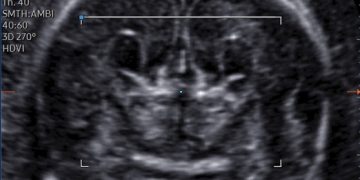

Cari soci, finalmente online le soluzioni dei casi del mese di Luglio Grazie a Carlotta Zorzi e Daniele Di Mascio!! Caso 1 - video [pdf-embedder url="https://www.sieog.it/wp-content/uploads/2024/07/risposta-Casodelmese_Luglio20241.pdf" title="risposta...